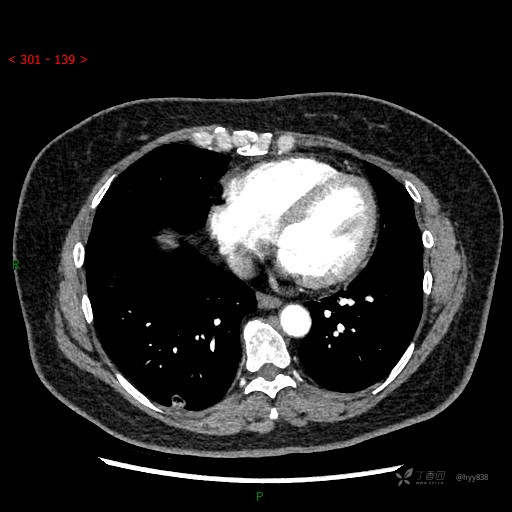

胸部CT平扫